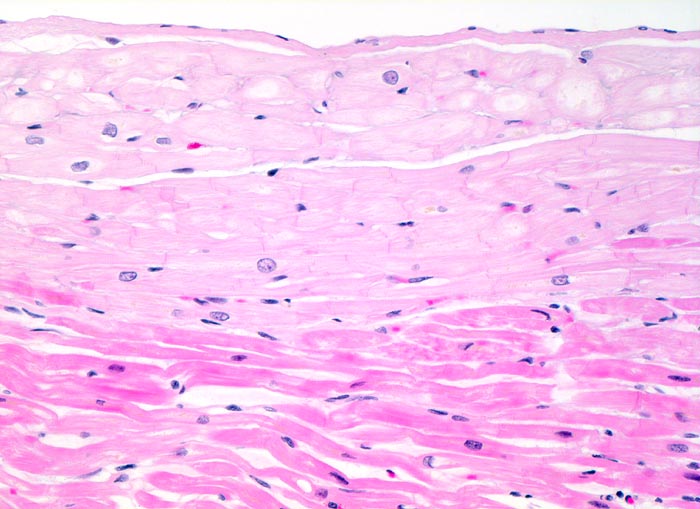

PathoPic ID 4126 - normales Myokard: Reizleitungszellen

normales Myokard: Reizleitungszellen

Subendocardiale Schicht von etwas grösseren deutlich helleren (herausgelöstes Glykogen) Herzmuskelzellen des Reizleitungssystems

200